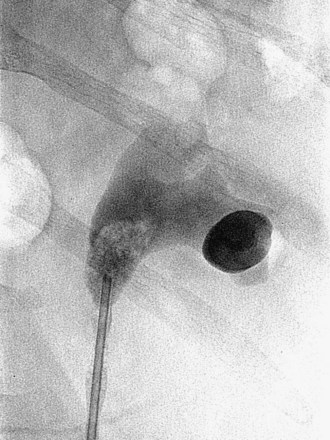

Figure 47–12 Occlusion balloon inflated and snugged down at ureteropelvic junction of contrast-filled upper tract collecting system.

), and a guidewire can be passed from below and grasped by the nephroscope to establish through-and-through access from the external urethral meatus to the percutaneous entry site. A dual-lumen catheter can be placed as well. The small caliber of either catheter, however, does not provide much outflow from the kidney and may not prevent stone or tumor fragments from passing into the ureter along the catheter. A ureteral occlusion balloon catheter, which incorporates an approximately 15-Fr spherical balloon on the distal tip, more consistently prevents material from migrating down the ureter. The balloon should be carefully inflated in the renal pelvis, making sure the balloon is not in the ureter—which could lead to ureteral rupture—and then gently pull down to occlude the ureteropelvic junction (Fig. 47–12). Another alternative is to place a ureteral access sheath (usually 11 to 15 Fr) over a retrograde-inserted guidewire (Landman et al, 2003). The large outer diameter of the sheath effectively prevents particles from passing around the sheath into the ureter, and the large inner diameter affords excellent outflow of small stone particles. The disadvantages of employing a ureteral access sheath include the potential ureteral trauma from passing such a large device into the ureter and clogging of the catheter lumen by oversized stone fragments.